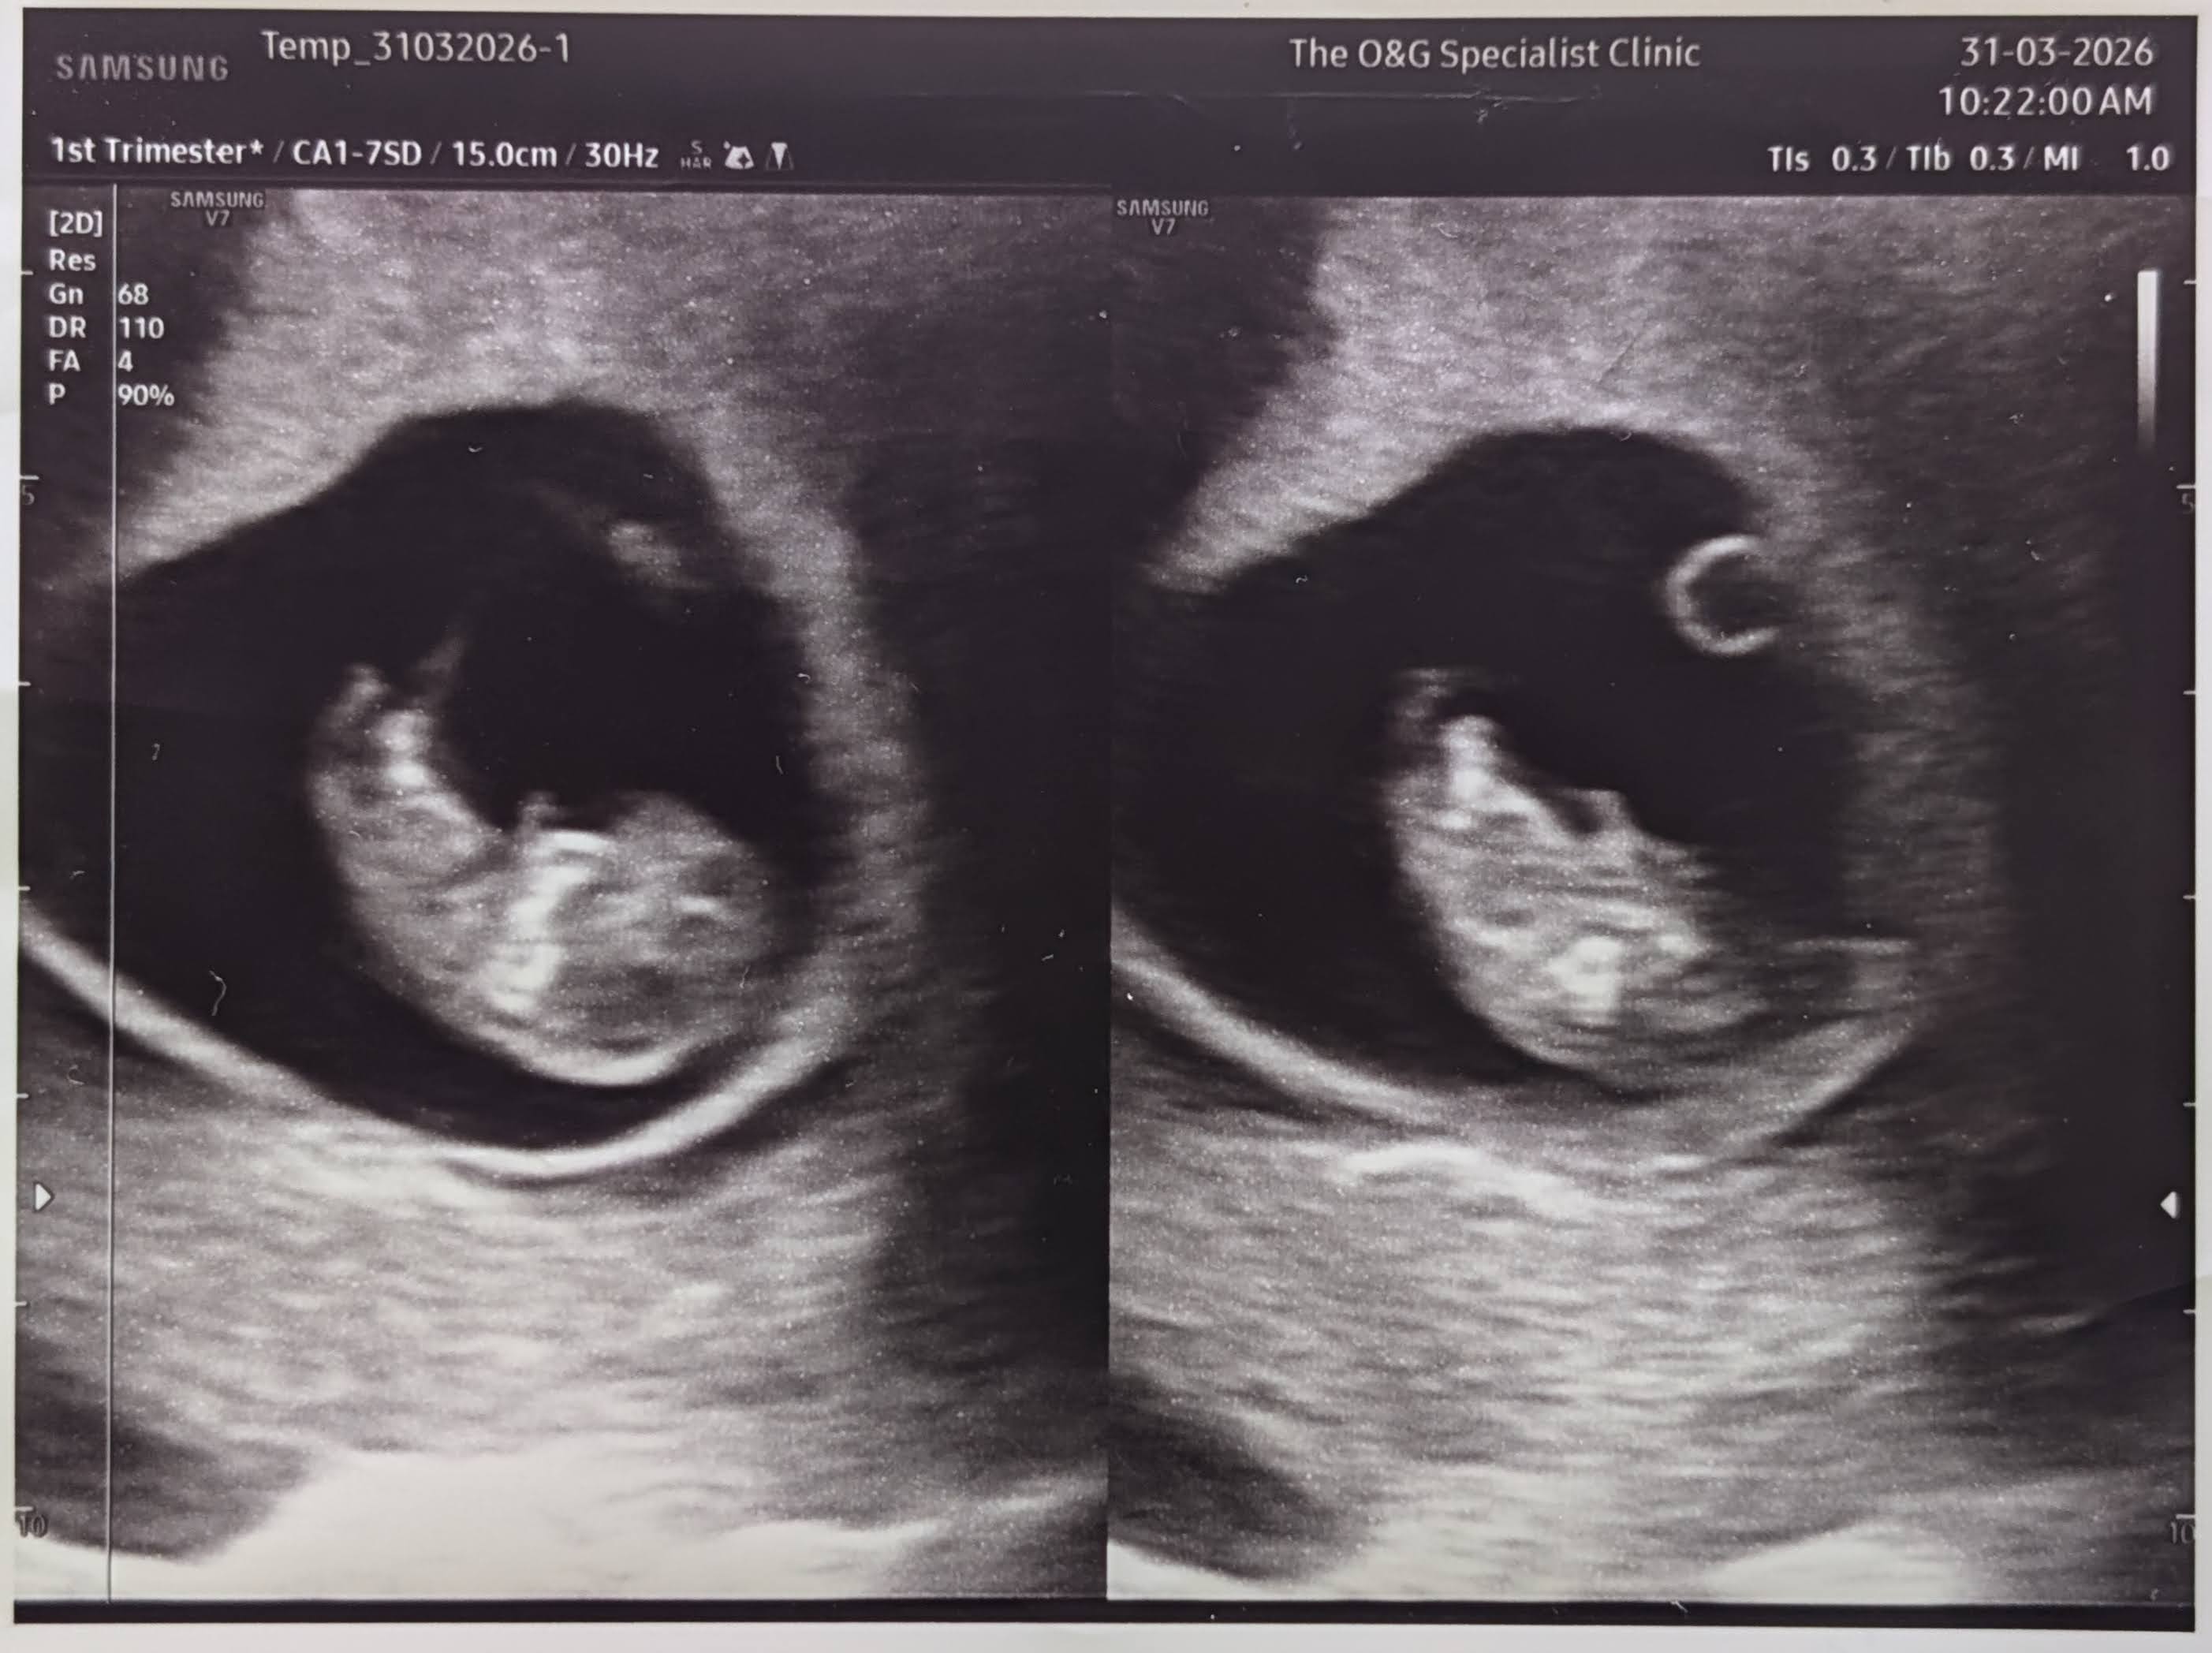

A little bun is in the oven! πΌ Coming November 2026